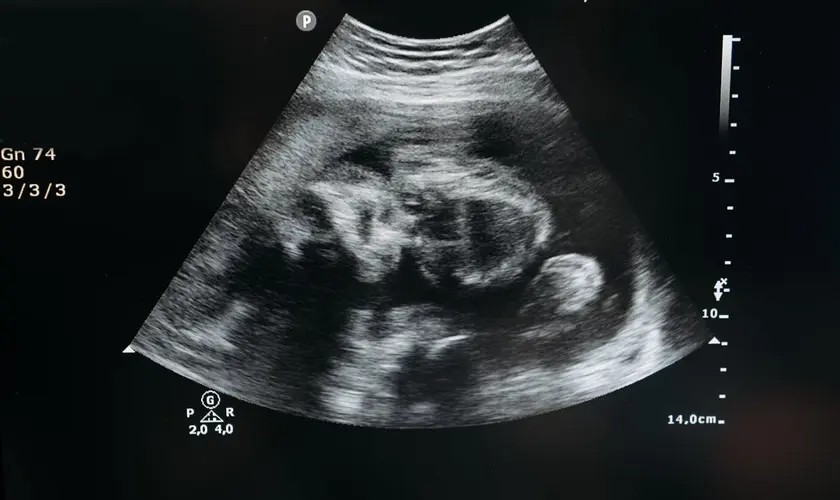

Em dezembro passado, Jenniffer González-Colón, governadora de Porto Rico, aprovou a Lei 183-2025, que altera o Código Civil porto-riquenho e reconhece o nascituro — um termo jurídico em latim que se refere a “concebido, mas não nascido” — como pessoa natural desde a concepção.

O Padre Carlos Pérez Toro, Pároco da Igreja de Santa Rosa de Lima, em San Juan, e advogado, participou como consultor jurídico na elaboração do novo Código Civil, e salientou que, graças a esta lei, “reconhece-se que o ser humano em gestação é uma pessoa natural desde o primeiro momento da concepção; usando um termo jurídico que só se aplica quando um ser humano nasce, diz-se que ele ou ela tem personalidade jurídica e capacidade desde o primeiro momento da concepção.”

“Graças a Deus, conquistamos o reconhecimento claro em Porto Rico de que o ser humano em gestação é uma pessoa natural com todos os direitos, como se já tivesse nascido. Imagine o que isso significa para a mãe que agora tem um novo instrumento para defender seu filho”, disse o Sacerdote, que explicou que toda gestante em Porto Rico agora pode designar seu filho ainda não nascido como herdeiro.

“O que esta lei faz é equiparar a criança no útero a uma criança que já nasceu. As perspectivas futuras que esta lei trará para um ser humano em gestação e para a mãe são inimagináveis”, disse o Padre. Ele indicou que, por exemplo, em questões tributárias, uma criança no útero pode ser declarada como um novo dependente para fins de pagamento de impostos em Porto Rico.

“Tudo isso se aplica ao ser humano em gestação”, disse o Padre e jurista, que também abordou as implicações culturais que essa lei terá entre os habitantes da ilha. “Aquilo não é uma célula, um zigoto, um feto, mas um ser humano”, frisou o Clérigo.